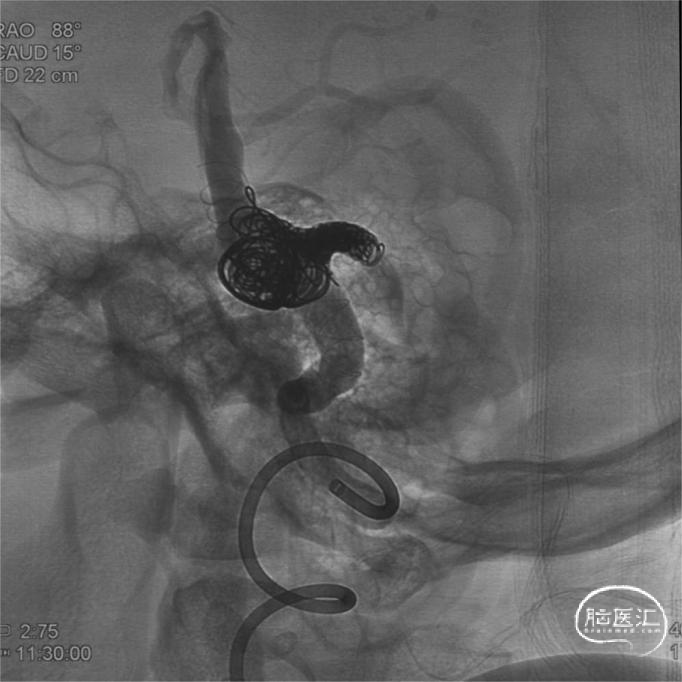

术后即刻

右侧椎动脉造影见血管重建满意;

术后右侧椎动脉正侧位造影:

左侧椎动脉正侧位造影:

术后C臂CT未见明确颅内出血。